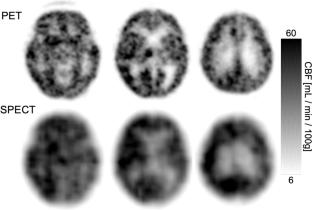

A 3D-PET/CT scanner, Discovery IQ, which has a 5-ring configuration with a 26 cm axial field of view, was used. A 100 mL saline pack containing 11C at 460 MBq was placed on a 3D Hoffman brain phantom (HBP) filled with 18F at 5.0 kBq/mL, and dynamic scans were performed. The quantitative capability of measured radioactivity in the HBP was evaluated. Subsequently, the HBP filled with 18F at 5.0 kBq/mL was equipped with a gas mask system, and 15O-gas was administered at flow rates ranging from 3000 MBq/min, decreasing in 500 MBq/min increments, while dynamic scans were performed. The quantitative accuracy of radioactivity in HBP and count rate characteristics were evaluated. To confirm the feasibility of the 15O-gas PET method in the clinical situations both practically and quantitatively, cerebral blood-flow (CBF) values obtained via PET and SPECT were compared in 10 patients with cerebrovascular diseases. CBF was calculated by the autoradiography method. Analyses included standard brain transformation and alignment, followed by averaging CBF values from 26 brain regions for comparison.

The measured radioactivity in the HBP approached the true value as the radioactivity of 11C in the saline pack decreased. To achieve a quantitative error within ± 5%, the radioactivity of 11C needed to be below 40 MBq. Similarly, for 15O-gas PET, an administration rate below 1000 MBq/min was needed to maintain quantitative accuracy within ± 5%. When exceeding 1500 MBq/min, random events surpassed 50%, compromising reliability. The correlation coefficient between PET and SPECT-derived CBF was 0.39 (p < 0.001). After excluding two outliers, it improved to 0.71 (p < 0.001), indicating a strong correlation. PET-measured CBF tended to be higher than SPECT.